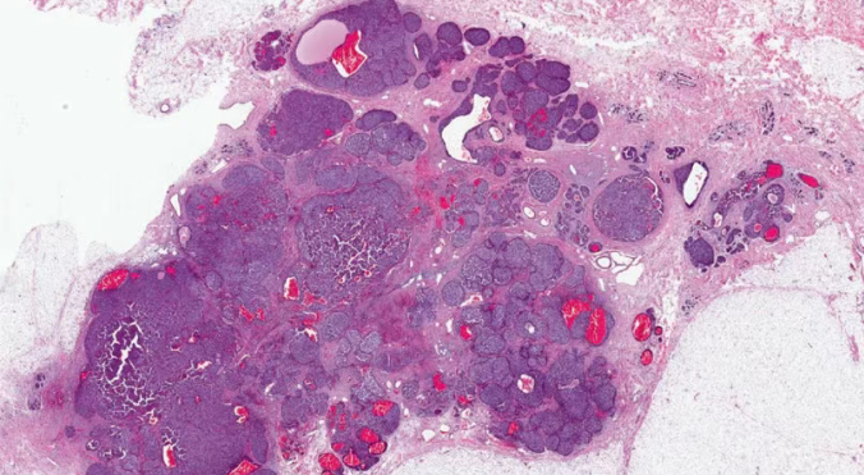

结构特点:轮廓清楚的实性结节纤细的血管轴心。

DCIS样,界限清楚、多个、膨胀性结节状

原位SPC:轮廓光滑的圆形结节结节周围无促结缔组织增生结节周围肌上皮可有可无

浸润癌两种浸润方式

1、浸润性实性乳头状癌:保留实性乳头状结构,体积大的团巢,轮廓不规则,间质促纤维反应,肌上皮缺失,原位SPC背景

2、实性乳头状癌伴浸润:轮廓圆滑的结节,伴有浸润性成分,包括粘液癌,NET,浸润性癌(NST)